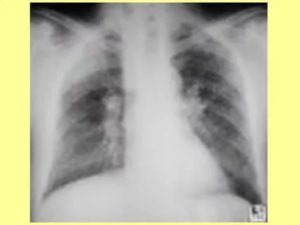

Основным признаком спаечного процесса на легком является наличие тени, которая появилась на снимке. Стоит учесть тот факт, что она никак не изменяет свою форму при вдохе и выдохе. Наряду с этим легочное поле будет менее прозрачным, а диафрагма и грудная клетка могут быть несколько деформированы. Зачастую спайки наблюдаются внизу легкого.

Для обнаружения легочных заболеваний в первую очередь используется флюорография. Эту процедуру необходимо проводить ежегодно, в основном она направлена на выявление ранней стадии туберкулеза. Однако опытный рентгенолог может выявить на снимке образовавшиеся плевральные спайки, которые выглядят тенями. Причем форма их не меняется в зависимости от вдоха и выдоха.

При необходимости дополнительно назначается рентген. Как правило, спайки располагаются в нижней части легкого. При этом будет более темная картинка, а также может быть частичная деформация грудной клетки и диафрагмы.

Основной атрибут, указывающий на спайку справа, является тень, видная на Rg-снимке. При этом затемнение не изменяется при вдохе и выдохе пациента. Одновременно снижается прозрачность легочной поверхности.

В тяжелых случаях наблюдается деформирование грудной клетки и диафрагмальной области. При таком состоянии диафрагма ограничивает свою подвижность. Чаще всего такие спайки расположены в нижних отделах легкого.

Распознать спайку по снимкам можно, если на нем легкие мутные, а еще при сравнении фотографий на вдохе и на выдохе. Спайка выглядит как тень, положение которой не меняется во время дыхания. Иногда наблюдается изменение формы и ограничение подвижности диафрагмы и грудной клетки.

Чаще всего спайки обнаруживают в нижней части легких.